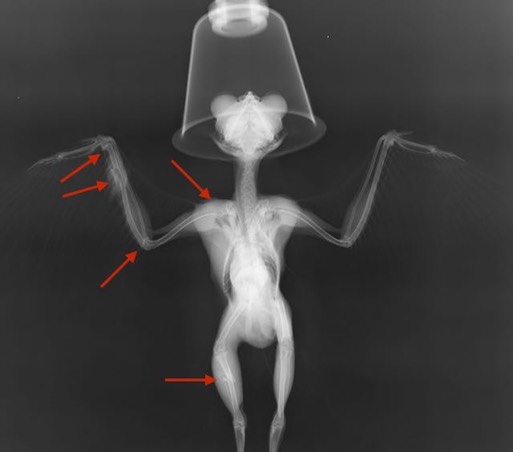

Western Screech Owl 17-680

This adult Screech Owl was found along a rural road and was likely hit by a car. His right wing and right leg were both broken.